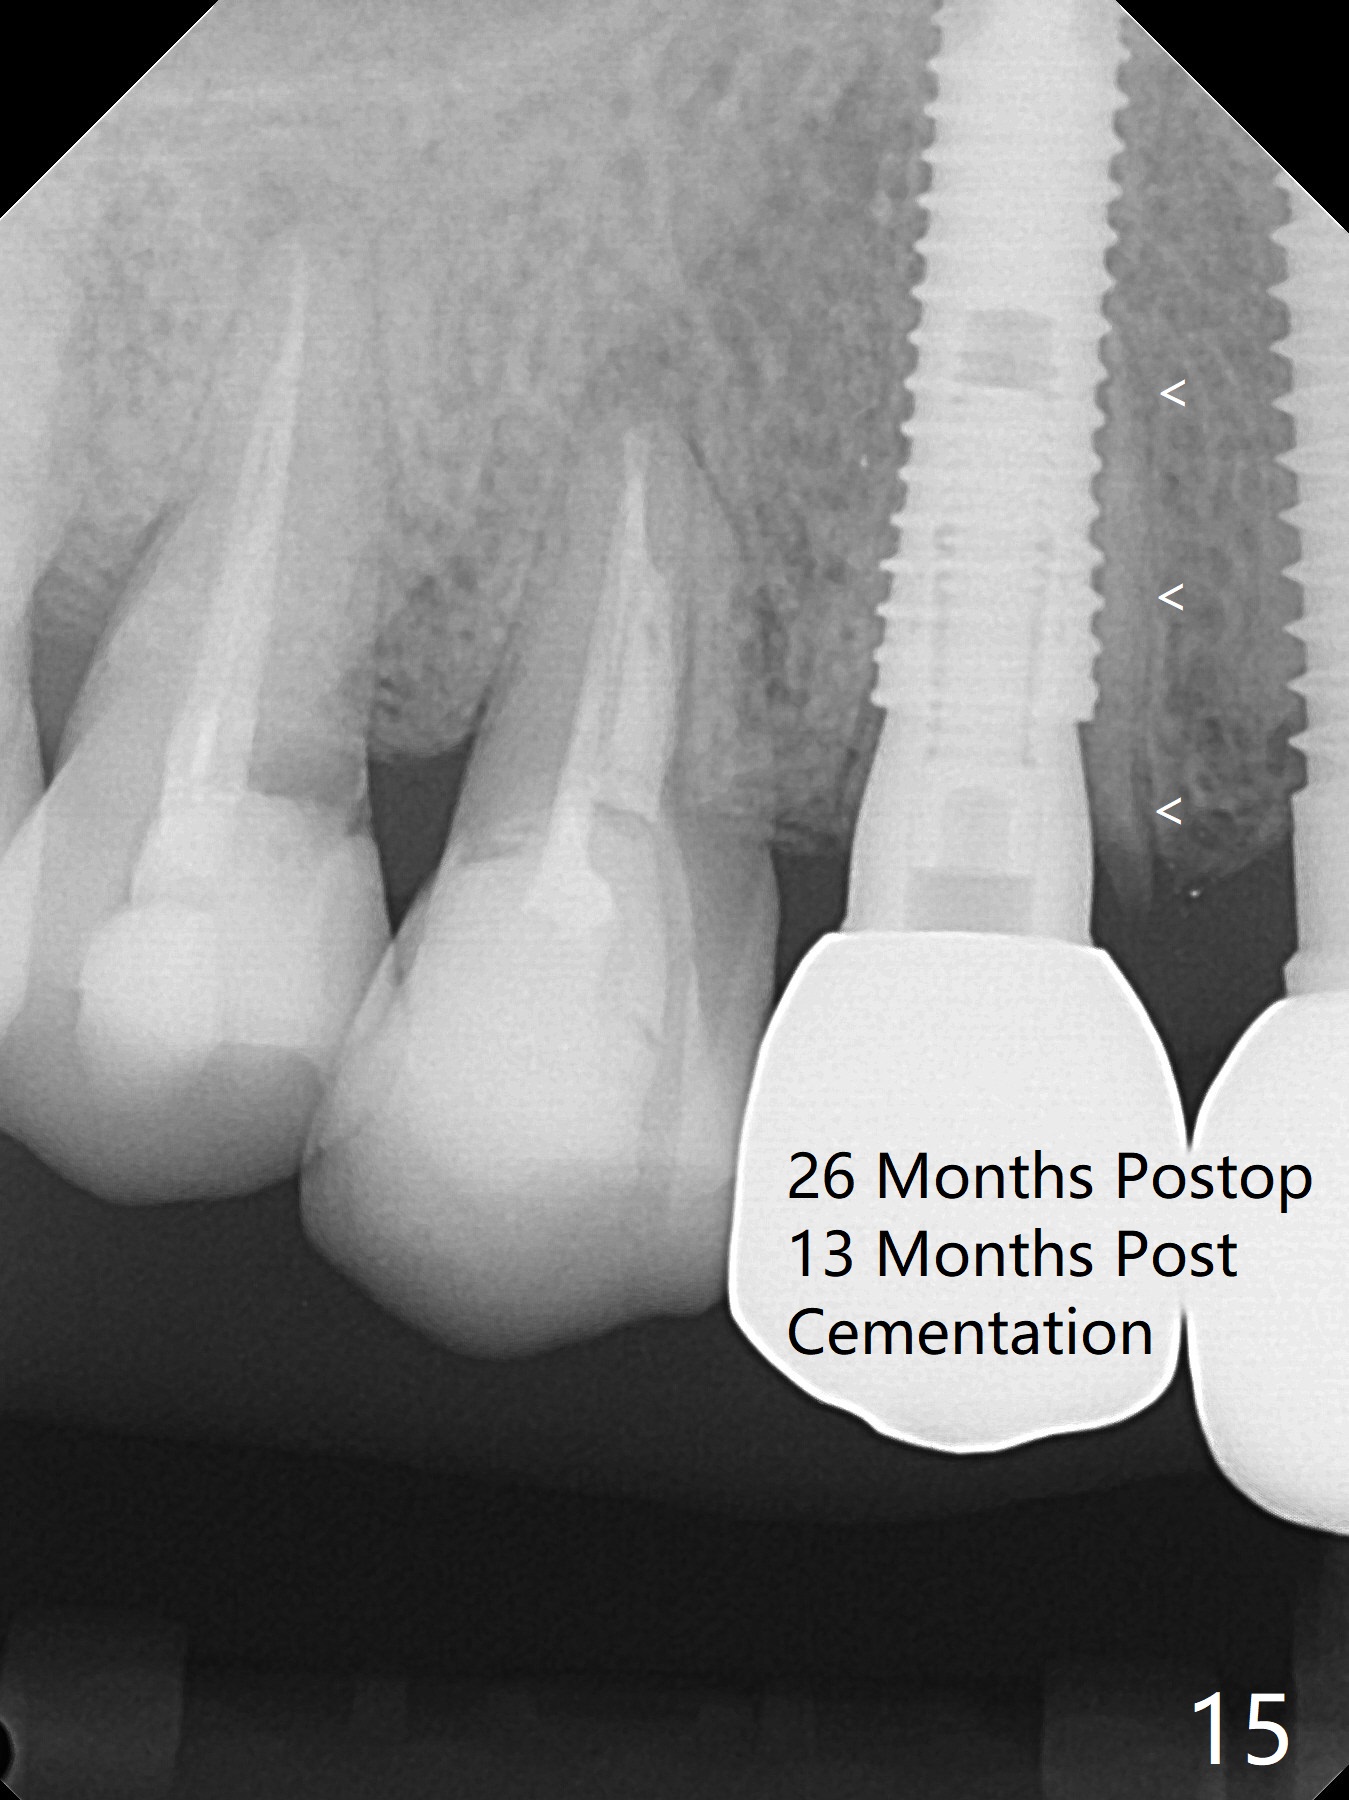

Since the ridge at #7 is ~ 4 mm, a 2.5x14 mm 1-piece implant is placed (Fig.8) after 1.2 mm (Fig.7), and 1.5 mm drills at 12 mm and 2 mm drill at 8 mm. Later the implant is placed deeper (Fig.10). There is no bone loss 7 or 12 months postop, respectively (Fig.11,12). After Diode gingivectomy, there is papillary formation (Fig.13). No provisional is provided after impression (with the abutment torqued at #6) for oral hygiene. With access holes at #6 and 7, crowns are bonded with minimal residual cement (Fig.14 <, which is removed later). There is no hard (Fig.15,16) or soft (Fig.17 *) atrophy 26 months postop, i.e., 13 months post cementation, due to the presence of socket shield (Fig.15 <, as compared to Fig.1). In fact the tooth #8 has mobility and fremitus (short root/poor crown/root ratio, Fig.16); occlusal adjustment is done 13 months post cementation. The crown is dislodged 2 years 1 month post cementation; a prefabricated post is being tried in (Fig.18). There is no atrophy, bone loss or infection at #6 (with socket sheath (*)) or 7 two years 5 months post cementation (Fig.20-27).